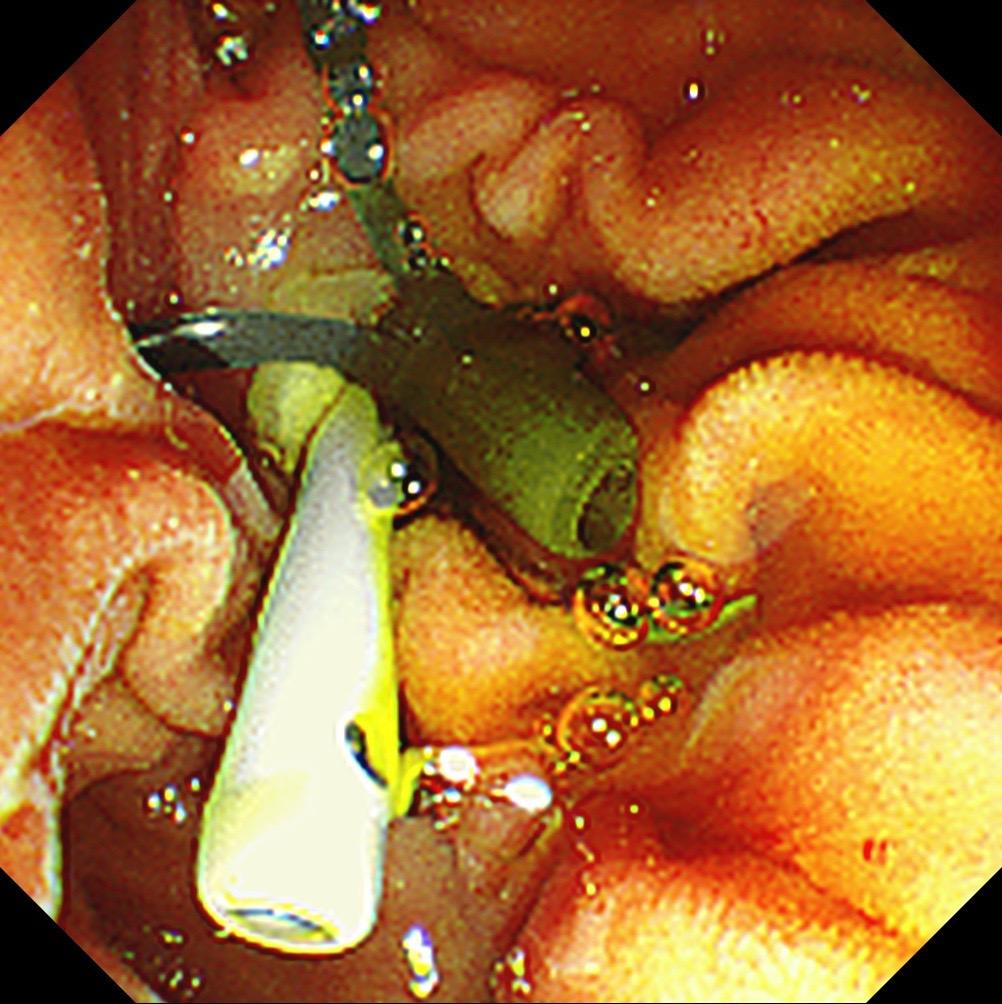

周末胆管结石化脓性胆管炎急诊ERCP.患者胆囊切除术后,这次因胆管结石腹痛来住院,患者一直服用阿司匹林没法直接手术,想让患者停够七天后再手术。住院第三天患者腹痛持续不缓解,黄疸升到快两百,没办法只能周末急诊手术,先放塑料支架解除患者的痛苦,下一次再取结石!患者家庭条件一般,想尽量帮患者省点花费,结果还是没办法……